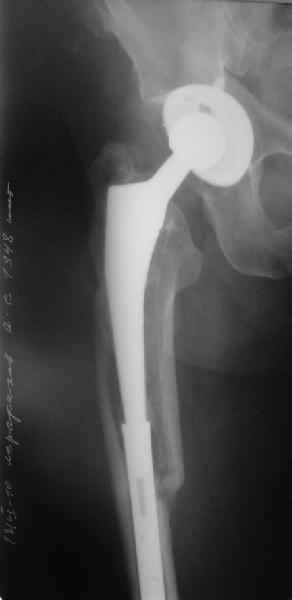

Уважаемые коллеги, продолжая дискуссию, начатую на "Вреденовских чтениях", хочу сказать, что принципиально сущестует два возможных варианта лечения.

1.Остеосинтез на ножке. Мне кажется, что применительно к этому случаю малоперспективный вариант. Синтез хорош, когда можно его выполнить в малоинвазивном исполнении и достигнуть стабильности. Действительно, если ножка б/цементной фиксации после этого не будет иметь фиксации, то ревизия не будет иметь проблем. В представленном случае стабильность синтеза сомнительная, а проведение доп.иммобилизации приведет к контрактуре суставов.

2. Применение ножки дистальной фиксации, мы отдаем предпочтение ножке Вагнера с фиксацией проксимального отдела на ножке. Более травматичное вмешательство, но при стабильной фиксации ножки реабилитация идет в обычном режиме.

Хочется показать два подобных случая, П-ка З. 72 лет и п-т Г. 80 лет. Сразу принимаю замечание, что это были ножки цементной фиксации, просто под руками не было бесцементника.

С уважением, Р.Тихилов

Пациента удалось осмотреть недавно. Достигнутый результат сохраняется. Перелом бедра сросся. Конечность опорная и безболезненная, ходит без трости. Ножка, похоже, реинтегрировалась, как и надеялись. Снимки и фото в приложении. Комментарии приветствуются.

Надо ли что-то делать дальше, как полагаете? Убрать винты? Убрать "удлинитель ножки"? Или оставить все, как есть? Спасибо заранее.